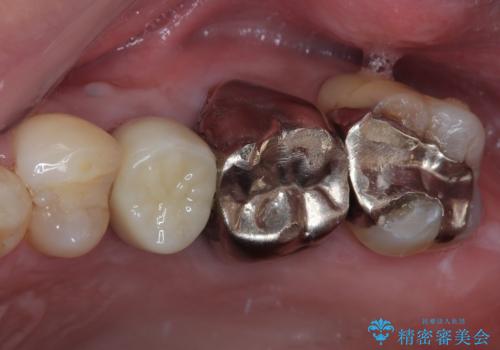

より審美的で、より機能的に優れた治療をご希望とのことであったので、ジルコニアカスタムアバットメントを用いたインプラント治療を行うこととしました。

ジルコニアカスタムアバットメントは、歯肉ラインに金属が見えにくいというだけでなく、クラウンを装着する土台の形が天然歯と近い形態となるため、清掃性が高く歯肉が腫れにくいというメリットがあります。

インプラントは、骨との生着能が比較的高いとさせるSLAタイプを使用しました。